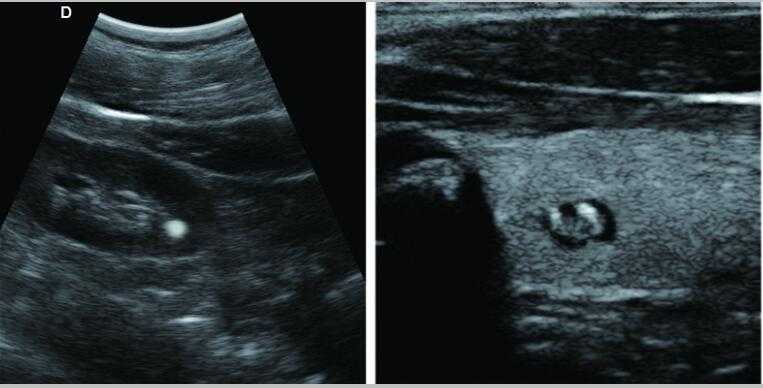

全數字彩色多普勒超聲診斷儀DW-PE522

1.組織諧波成像技術 2.噪聲抑制斑點技術 3.多波束并行處理技術等

7.應用:腹部、婦科、產科、心臟、血管和小器官、泌尿科、肌肉骨骼、兒科等